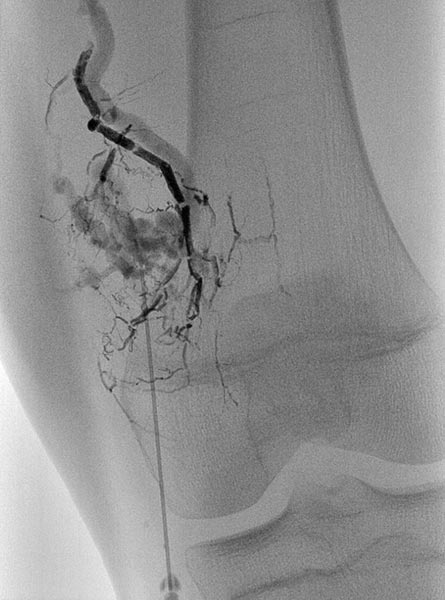

Digital subtraction angiography (DSA) in the early arterial phase shows a dilated feeding artery (so-called “feeder artery”), in this case a medial superior genicular artery. This artery is dilated over time due to chronic hyperperfusion with increased blood flow.

Digital subtraction angiography (DSA) in the arterial phase 2 s later shows some minor arteriovenous fistulas.

Digital subtraction angiography (DSA) in the interstitial and early venous phase again 4 s later shows no direct early venous outflow of the contrast agent but, instead, a pooling phenomenon. In an arteriovenous malformation, an immediate venous outflow would be seen because of multiple direct arteriovenous communications.